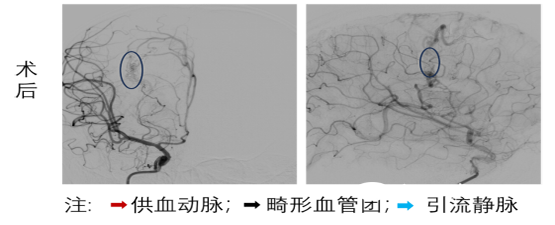

面对生命垂危的患儿,姚声涛教授团队组织全科讨论,制定详细的治疗方案,采用介入动静脉畸形栓塞术。手术无需开颅,仅通过患儿大腿根部的股动脉做一个微小穿刺口,在DSA的引导下,将一根纤细的微导管精“导航”至大脑深处的畸形血管团内。随后,向畸形血管团内注入特殊的“生物胶”栓塞剂,让药剂在血管内部层层填满、牢牢“堵死”这个异常的血管“短路”,从根源上消除再次出血的隐患。凭借团队娴熟的操作技巧和精准的治疗决策,两台手术均顺利完成,整个手术过程精准微创,最大程度减少了对患儿脑组织的损伤,为术后快速恢复打下了基础。